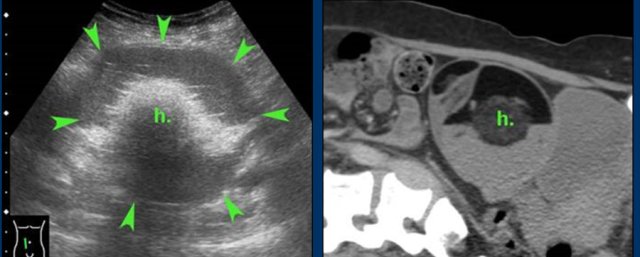

case 5 - Actinomycosis

A 52-year old woman presented with RLQ pain for two weeks.

US and

subsequent CT, showed a large, right sided iliopsoas abscess (absc.), in continuity

with a TOA, causing hydronephrosis with cortical loss and a dilated ureter (u.).

There was an IUD in the uterus, the CRP was 240 and the WBC 26.

The

IUD, that had been in place for 30 years, was removed.

The abscess was punctured

and later drained percutaneously.

Gram

stain of the pus showed gram-positive rods, suggestive of actinomycosis, and

i.v. penicillin was started.

Cultures grew Actinomyces israelii 20 days later.

Eventually there was a complete cure without residual abnormalities.